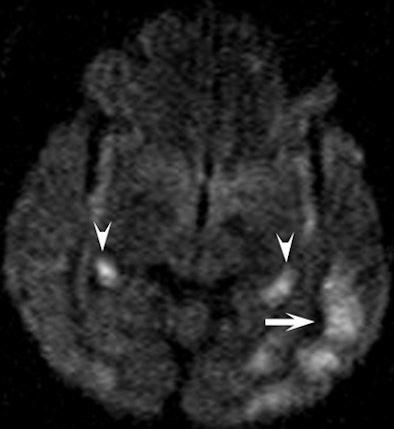

| Clinical images of a 51-year-old man found unconscious with a Glasgow Coma Scale score of 7 and withdrawal to pain. Above image shows fluid-attenuated inversion recovery, while below is a diffusion-weighted image that shows an increase in signal intensity in the head, body, and tail of the hippocampus bilaterally (arrowheads) and in the cerebral cortex (arrow). All images courtesy of Radiology and the National Neuroscience Institute. |